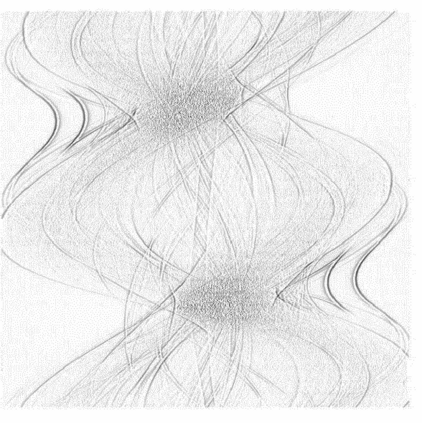

Low-Dose Computed Tomography (LDCT) technique, which reduces the radiation harm to human bodies, is now attracting increasing interest in the medical imaging field. As the image quality is degraded by low dose radiation, LDCT exams require specialized reconstruction methods or denoising algorithms. However, most of the recent effective methods overlook the inner-structure of the original projection data (sinogram) which limits their denoising ability. The inner-structure of the sinogram represents special characteristics of the data in the sinogram domain. By maintaining this structure while denoising, the noise can be obviously restrained. Therefore, we propose an LDCT denoising network namely Sinogram Inner-Structure Transformer (SIST) to reduce the noise by utilizing the inner-structure in the sinogram domain. Specifically, we study the CT imaging mechanism and statistical characteristics of sinogram to design the sinogram inner-structure loss including the global and local inner-structure for restoring high-quality CT images. Besides, we propose a sinogram transformer module to better extract sinogram features. The transformer architecture using a self-attention mechanism can exploit interrelations between projections of different view angles, which achieves an outstanding performance in sinogram denoising. Furthermore, in order to improve the performance in the image domain, we propose the image reconstruction module to complementarily denoise both in the sinogram and image domain.